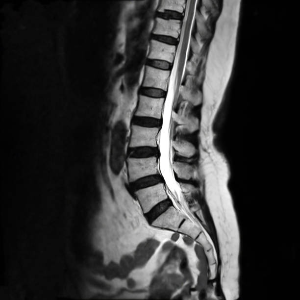

*실제로 디스크 탈출의 흔한 동작이 동전을 줍거나 뒤로 돌아보는 동작에서 손상이 발생.